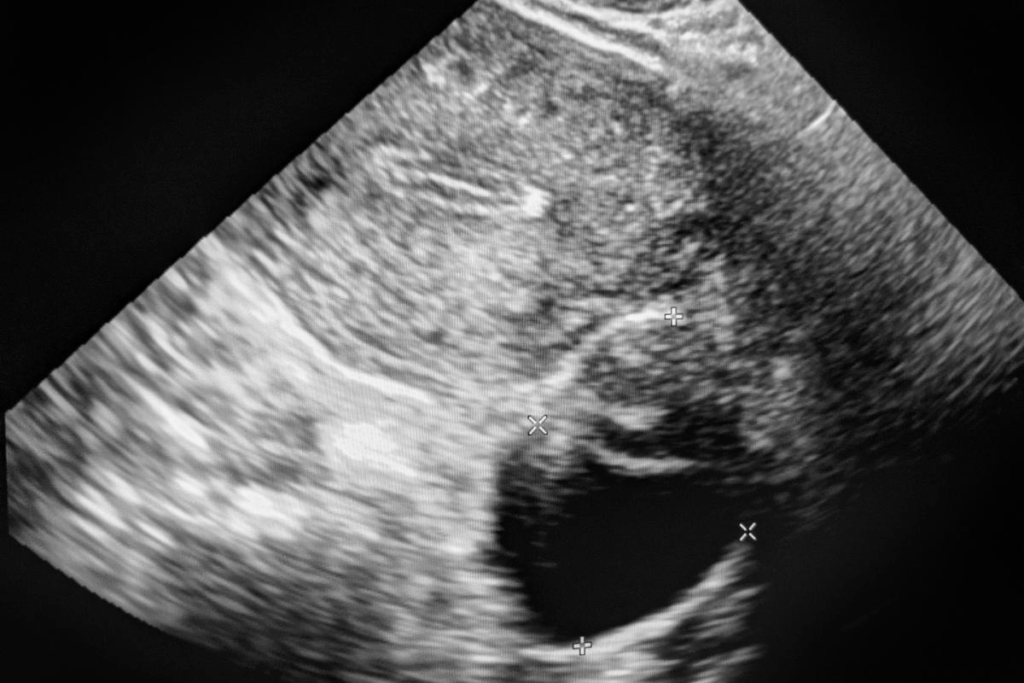

• MRI (Magnetic Resonance Imaging) to see the fibroids and uterus

• Ultrasound to look at the uterus and fibroids